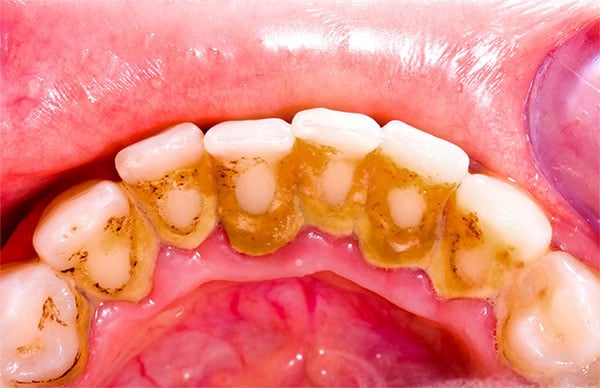

Diş taşı nedir?

Uzun süredir dişte bulunan plağın sertleşmesiyle oluşan yapıdır. Rengi sarı veya kahve rengi olabilir. Diş taşı oluşumu tükrük yapınıza, yaşa, ağız bakımınıza ve beslenme şeklinize göre değişkenlik gösterir.

Diş taşı pürüzlü yapısı nedeniyle daha çok plak birikimine sebep olur.